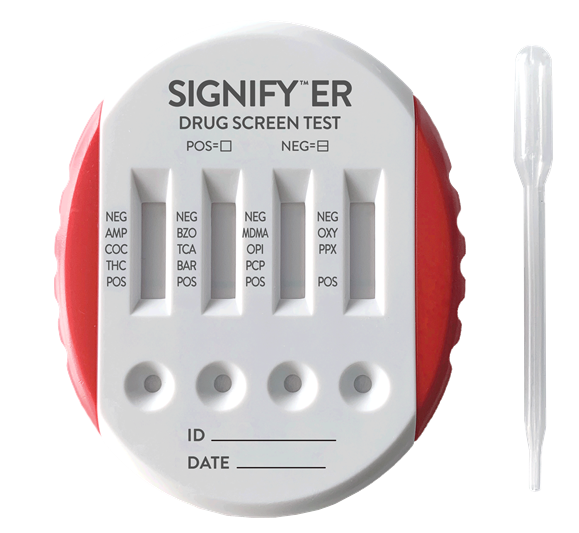

薬物検査 乱用薬物の実態 密造から化学式まで 法科学鑑定研究所

Signify Er 製品ラインナップ シスメックス プライマリケア

尿中薬物スクリーニングテスト 薬毒物分析キット 簡易分析キット 分析 関東化学株式会社